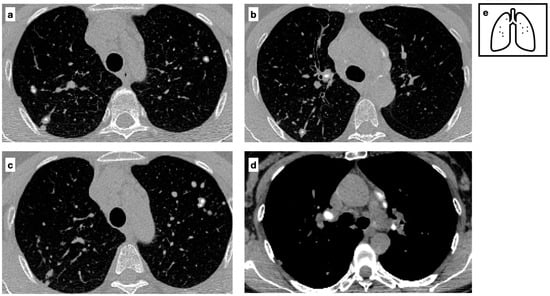

Figure 9.

CT axial images demonstrate a peripheric lung nodule characterized by spiculated margins, small cavitation and an eccentric calcification; this lesion was a biopsy-proven adenocarcinoma (a,b). Heavy smoker patient with severe confluent centrilobular emphysema. HRCT shows a malignant nodule with a small eccentric calcification in the right upper lobe (c). A spiculated nodule with a relatively fast growth rate must always raise the concern for lung cancer in patients with smoking history. Pattern of calcification (d).